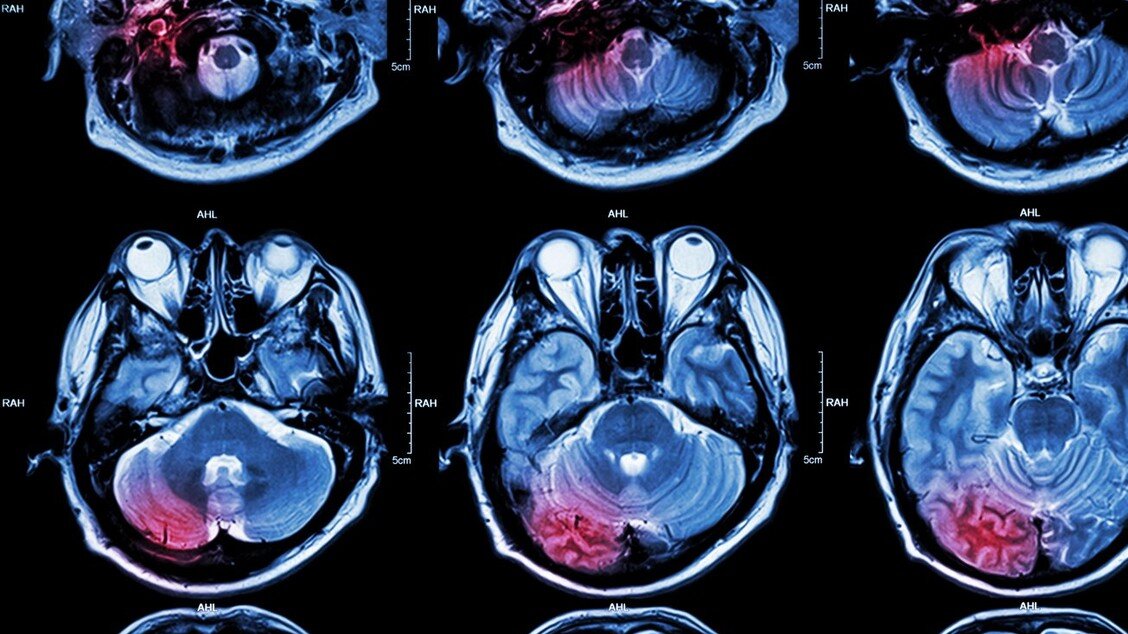

Foto: Shutterstock/ChaNaWiT